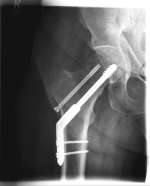

Oberschenkel 1          Oberschenkel 2

Images: Here is the supply of a dynamic hip screw shown.

In younger patients and a minor shift, the goal is to preserve the femoral head. The blood supply to the femoral head is at risk for medial femoral neck fractures, so that the fastest possible care should be sought if one wants to preserve the femoral head. Among others, the dynamic hip screw (DHS) is available for this purpose.